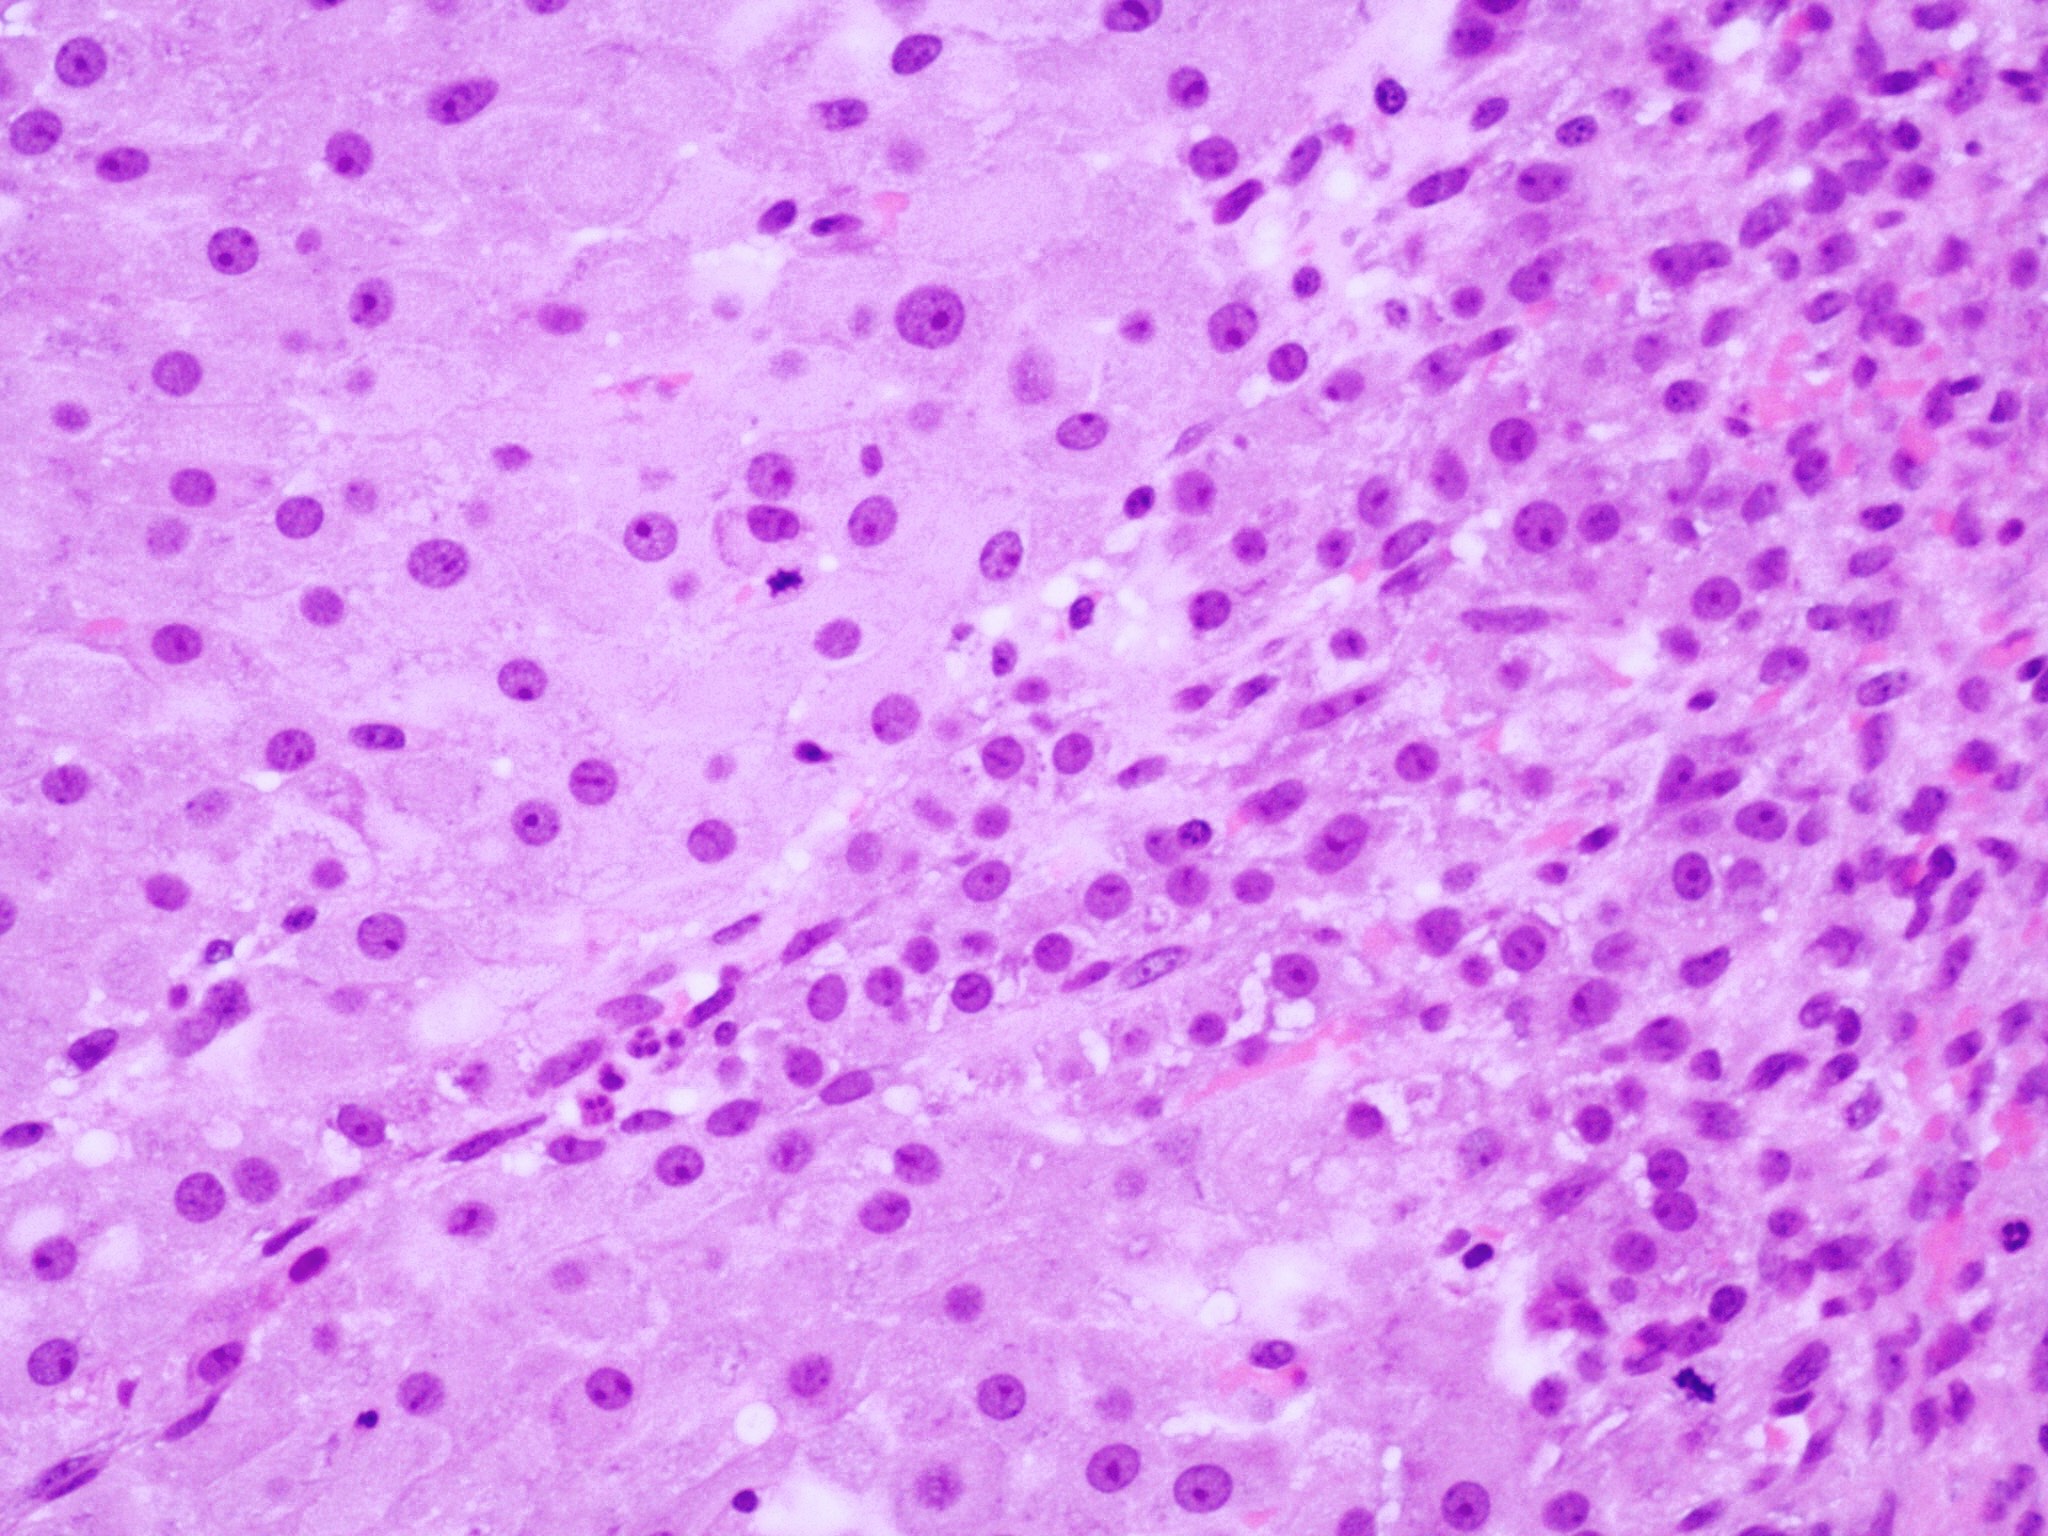

Microscopic (histologic) description

- Cyst lining is convoluted, composed of an inner layer of luteinized granulosa cells and outer layer of theca cells

- Granulosa cells are polygonal in shape, with abundant eosinophilic cytoplasm and central round nuclei

- Mitotic figures may be seen in the granulosa cells

- Outer theca cells are smaller in size

- Prominent inner layer of fibrous tissue

- Reference: Kurman: Blaustein's Pathology of the Female Genital Tract, 7th Edition, 2019

Microscopic (histologic) images